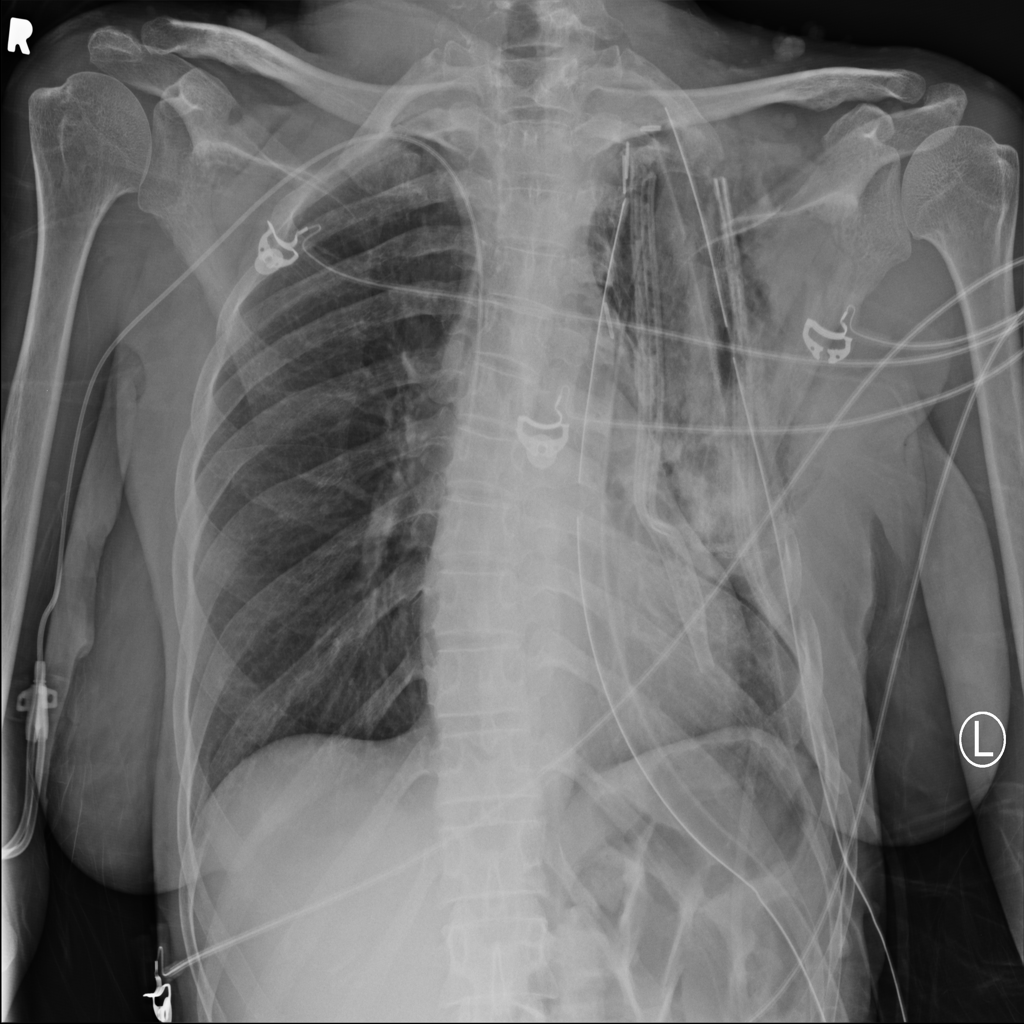

PAT-B0DB · IMG-003Emphysema

PAT-B0DB · IMG-003

PA